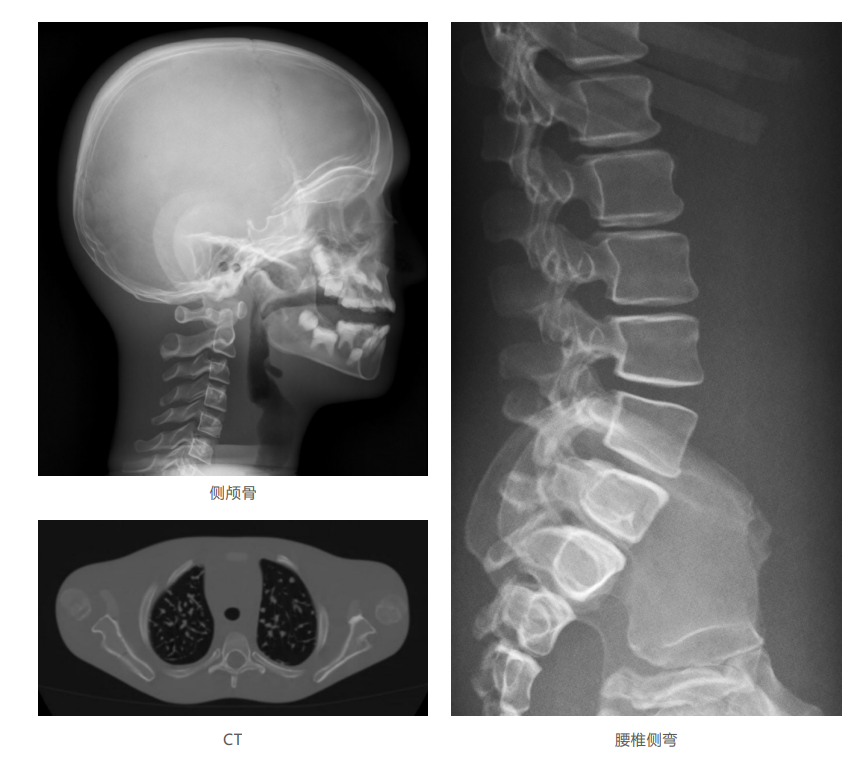

模體掃描成像圖:

仿真兒童培訓模體旨在幫助教學和提高患者對體位、準直和解剖學的理解,其廣泛的特點有助于安全、高質量的兒科影像學的有效指導。 模體的大小和結構都代表了典型的5歲兒童,使其便攜和易于定位。包括頭、胳膊和腿在內的整個身體高110厘米,重20公斤。該系列包括六個部分的模體可單獨或作為一個完整的集合。 右肢有伸直或彎曲兩種配置。左臂和左腿可選伴有或不伴有內嵌骨折。 骨折版本包含最常見的兒科骨折類型,包括脛骨扣帶骨折和腓骨普通骨折;第一跖骨骨折;橈骨切開復位骨折,第二中間趾骨常見骨折。 組件由適當的聚氨酯和環(huán)氧材料制成,模擬人體組織的 X射線衰減特性,用于診斷和治療能量范圍(50 keV - 25 MeV) 。 材料經久耐用,耐沖擊,適合連續(xù)搬運。透明的軟組織有助于解剖標志的視覺指示。